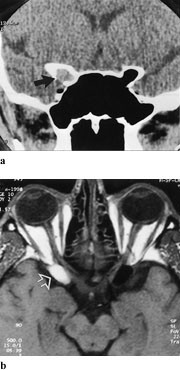

CT er mindre sensitivt ved nevritt, men kan vise fortykkede nerver, eventuelt med kontrastoppladning. Funnet kan være vanskelig å vurdere. Diagnosen av optikusnevritt kan ved MR dels baseres på volumøkning, i tillegg er økt signalintensitet i synsnerven på T2-vektede bilder eller kontrastoppladning på T1-vektet bilde karakteristisk (fig 4). Bruk av fettsuppresjon med såkalt ”short time inversion recovery” (STIR) og ved ”frequency spesific selective partial inversion recovery” (SPIR) øker den diagnostiske sensitiviteten av MR fordi nerven bedre skilles fra omgivende fettvev og fordi patologiske signalendringer derfor lettere kan sees (2). Bruk av kontrast kan gi noe varierende signalendring ved bruk av STIR, mens SPIR tryggere kan kombineres med kontrast (3). Bruk av FLAIR (fluid attenuated inversion recovery) (4) kan vise signaløkning i området med betennelse. Lesjonens utbredelse og varighet er avgjørende for graden av normalisering av visus. Gadoliniumkontrast vil tydelig vise blod-hjerne-barriere-skade i form av oppladning, eventuelle før kliniske symptomer oppstår. Dette sees både ved demyeliniserende, vaskulær eller stråleindusert optikusnevritt (5). Utvidede subaraknoidalrom er viktige tilleggstegn ved nevritt og kan fremstilles i så vel aksiale som koronale MR-snitt.

CT viser homogen fortykkelse av synsnerven både i aksial- og koronalplan. Hvis CT benyttes, hører koronale snitt med, og man bør undersøke uten og med intravenøs kontrast. Selve nerven kan ikke sees som en separat struktur, ikke engang etter kontrast. Utvidelse av optikuskanalen er vanlig. MR viser enten fusiform, eksentrisk eller tubulær fortykkelse (fig 5a). T1-vekting viser lik intensitet mellom tumor og nerven, mens T2-vekting viser økt signal. Kontrastopptaket er ofte beskjedent. Ved intrakranial utbredelse sees fortykkelse av chiasma, med lav signalintensitet på T1- og økt signal intensitet på T2-bilder (fig 5b). Fettsuppresjonsteknikk er nødvendig for å skille kontrastoppladning i tumor fra høyt signal i orbitalt fett.

CT viser diffus fortykkelse av synsnerven, med kraftig kontrastopptak i tumor. Forkalkninger styrker differensialdiagnosen. Det er vanskelig å påvise kalk ved MR, og derfor er begge metodene til nytte. Ved MR har svulsten lavere intensitet enn selve synsnerven (fig 6 a). Små meningiomer kan som regel påvises bare ved bruk av gadoliniumkontrast, og gir kraftig kontrastoppladning (fig 6 b). Denne metoden fremstiller også best eventuell intrakranial utbredelse av tumoren (7). Den beinete optikuskanalen kan være utvidet. Ordinære skjelettbilder av foramen optici er i dag oftest erstattet av tynne CT-snitt i to plan.